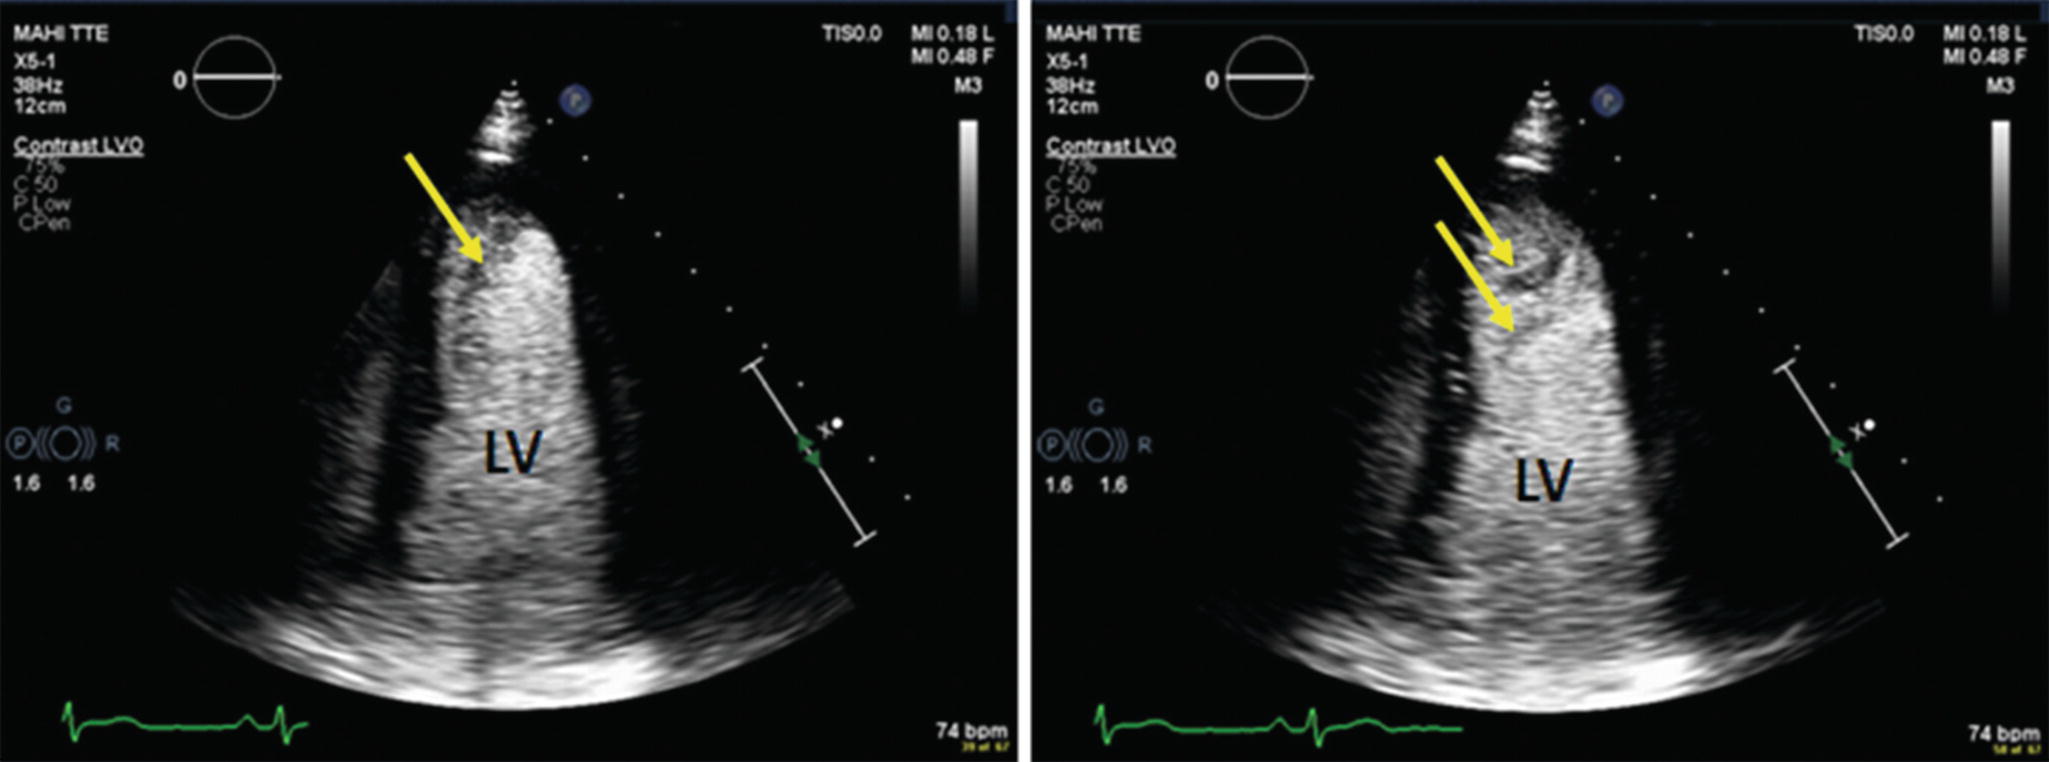

What is contrast echocardiography. Contrast echocardiography is a type of echocardiogram which is a cardiac ultrasound and can also be called an echo. By adding a contrast a cardiac echo has better resolution. The additional clearer resolution allows doctors to watch blood flow through the heart.

This will be carried out by an echocardiographer someone trained to perform. Contrast echocardiography is a technique for improving echocardiographic resolution and providing real time assessment of intracardiac blood flow. Agitated saline contrast provides contrast in the right heart and enables detection of right to left shunts.

Contrast echocardiography is used to delineate structures not readily seen superior and inferior vena cava descending aorta right ventricular outflow tract pulmonary arteries as well as to evaluate intracardiac shunts regurgitant lesions and complex congenital heart problems. Contrast echocardiography uses microbubbles by agitating approximately 8 cc of saline between two 10-ml. This paper examines the evidence for contrast echocardiography both for improving assessment of left ventricular structure and function compared with unenhanced echocardiography and for the identiļ¬-cation of myocardial perfusion.

Transpulmonary contrast agents are used to opacify left heart chambers eg. For enhancement of left ventricular endocardial border definition. Difficult Doppler signals can also be enhanced with echocardiographic contrast agents.